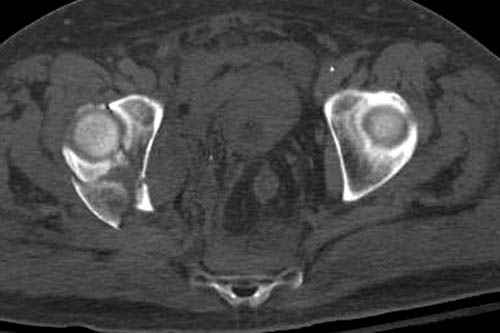

Дополнительно имеется перелом ацетабулума: задняя

колонна с полупоперечным переломом, и переломы костей лица.

На седьмой день зафиксирован перелом ацетабулума через задний доступ. Перед операцией для профилактики DVT, IVC фильтер, также получает Lovenox.

Извиняюсь за качества снимков, обычный больной в 300 фунтов, портативным ренген аппаратом не пробить.